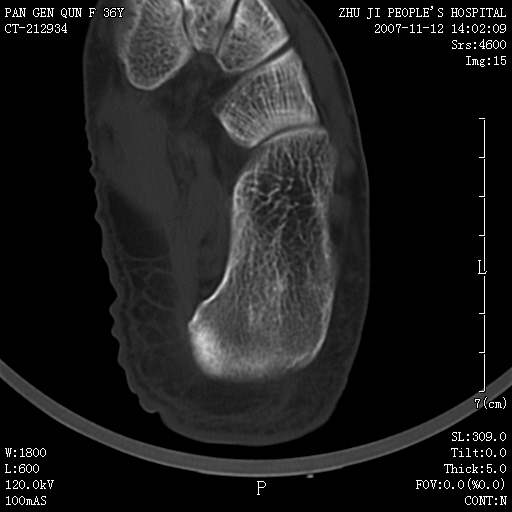

标题: CT10417:F36Y,跟骨跟腱附着处下方骨质密度影,请会诊. [打印本页]

标题: CT10417:F36Y,跟骨跟腱附着处下方骨质密度影,请会诊.

跟骨结节后部肿块半年,无明确外伤史,及红肿热痛.

附丽病:是指肌腱、关节囊、韧带于骨附着处的骨化和骨质侵蚀改变,常见于坐骨结节、髂骨嵴、坐骨耻骨支、股骨大小粗隆、跟骨结节等处。

x线表现为具有骨密度的细条索状影自骨面伸向附近的韧带、肌腱,宛如浓厚的胡须,以病变晚期更为明显,并有局部骨质侵蚀。

如果是骨瘤,也应该是骨旁骨瘤。发生部位不支持骨瘤,骨肿瘤提倡临床、放射、病理三结合诊断。